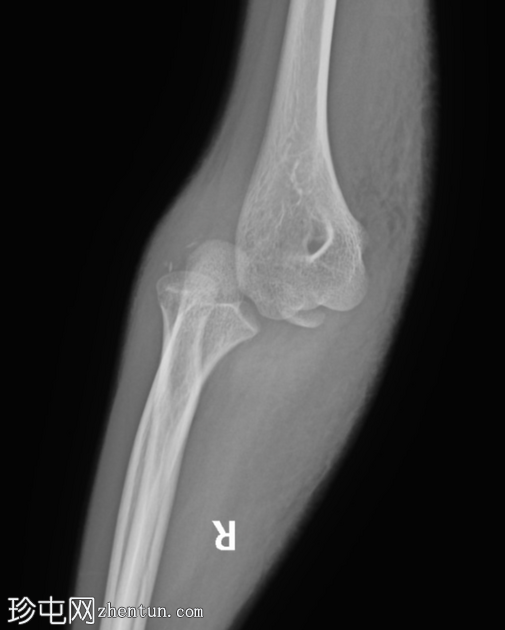

闭合复位后

X线片

3.png

正位片

4.png

侧位片

两个投照角度均显示肘关节复位良好。

复位后,骨碎片被明确识别为未完全骨化的内上髁骨折。

肘关节内仍有积液。